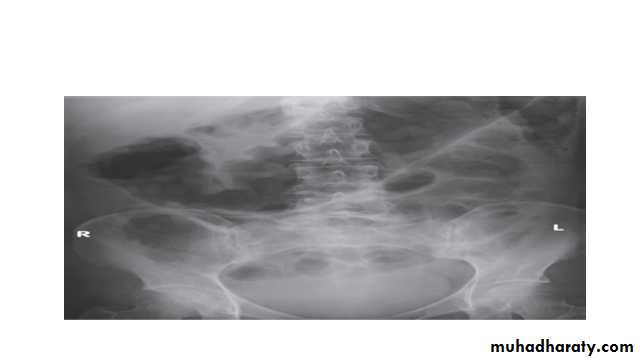

Life-threatening colonic inflammation:This can occur in both ulcerative colitis and Crohn’s colitis. In the most extreme cases, the colon dilates (toxic megacolon) and bacterial toxins pass freely across the diseased mucosa into the portal and then systemic circulation.

An abdominal X-ray should be taken daily because, when the transverse colon is dilated to more than 6 cm, there is a high risk of colonic perforation.

A plain abdominal X-ray is essential in the management of patients who present with severe active disease. Dilatation of the colon , mucosal edema (thumb-printing) or evidence of perforation may be found.